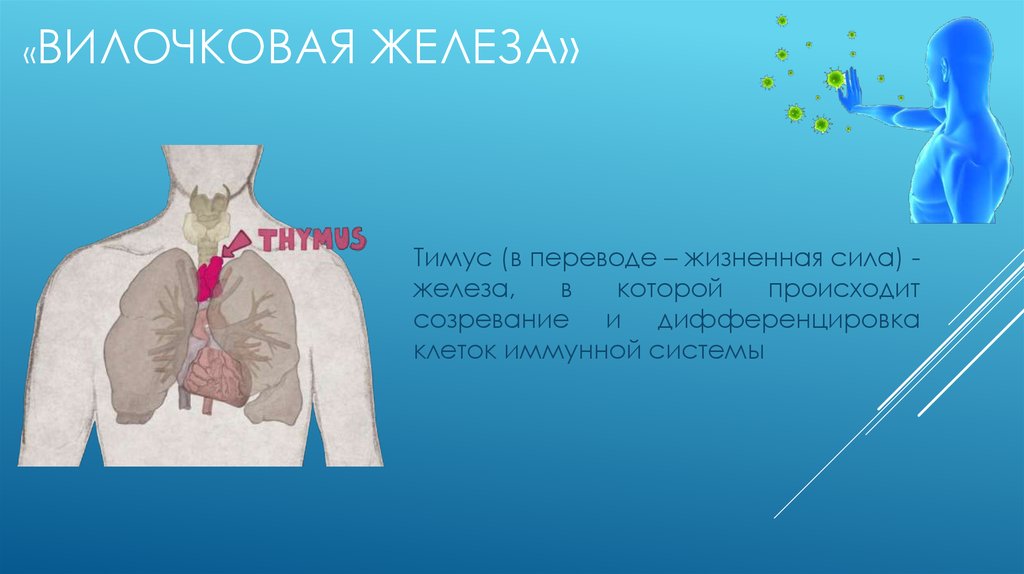

Фотографии вилочковой железы тимуса: структура и функции